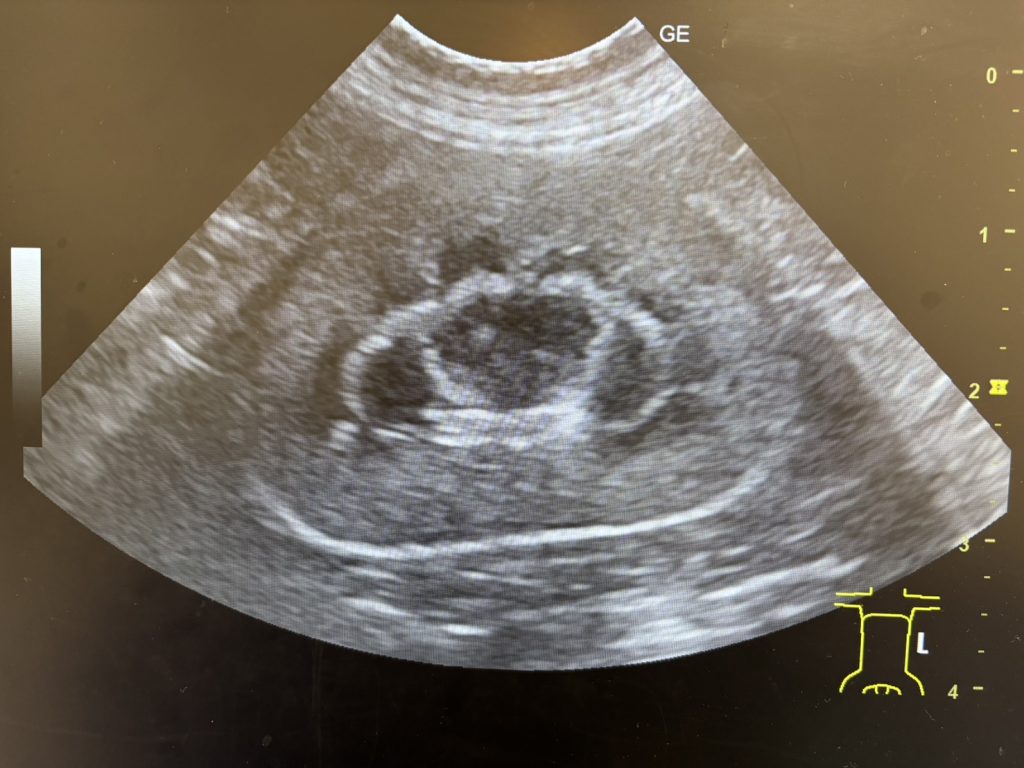

【正常な猫の腎臓】

水腎症とは?

尿管が結石などで閉塞すると、腎臓で作られた尿が流れなくなります。

すると尿が腎臓の中にたまり、腎臓が腫れる状態になります。

この状態を水腎症(すいじんしょう)と呼びます。

水腎症が長く続くと腎臓に強い負担がかかり、腎機能が低下する可能性があります。

猫の尿管閉塞では、超音波検査でこの水腎症が見つかることで

尿管結石が疑われるケースも少なくありません。